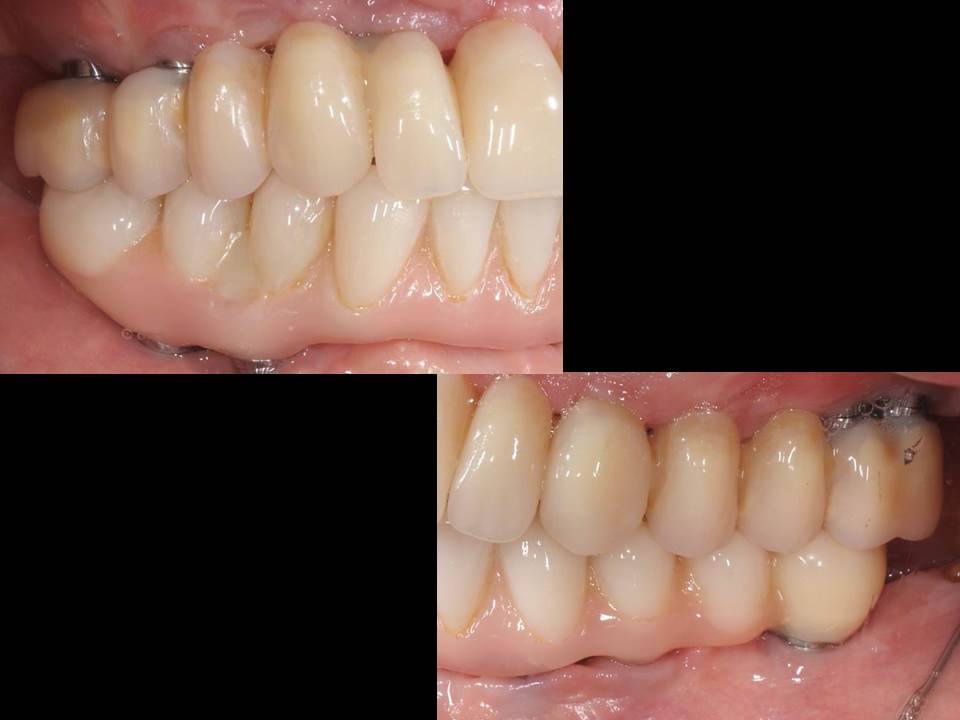

Prótesis fija OT BRIDGE

CASOS CLÍNICOS